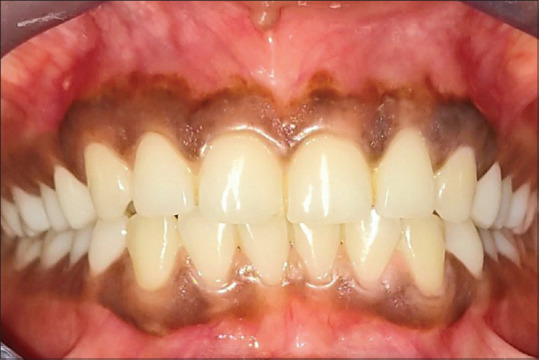

Materials and methods: Individuals with complaint of black gums were included. Informed consent was obtained. Initial treatment of scaling and root planing was conducted and they were recalled after 2 weeks. The gingival depigmentation was performed by scalpel technique. The excised layer of epithelial tissue was sent to the laboratory to assess the Tyr and TRP-1 levels. Subsequently, Vitamin C was administered at monthly interval for 6 months. Tyr and TRP-1 levels were assessed at the end of 1 year follow-up.

Results: The levels of Tyr and TRP-1 in gingival tissue at baseline and at the end of one year follow-up are shown in the table and graph. Tyr and TRP-1 levels were reduced after vitamin C administration.

Conclusion: Vitamin C administration resulted in reduction of tyrosinase and TRP-1 levels in human gingiva at 1 year follow-up indicating that Vitamin C is a probable inhibitor of melanin synthesis.